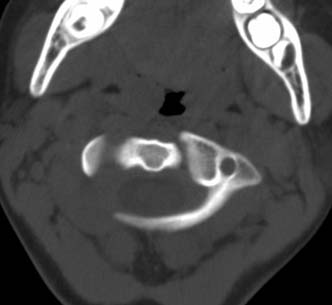

患者在校与同龄孩子打闹后(据家长说被拳击中颈部)出现颈部不适30分钟后入院检查,来时脖子歪斜。请大家看看枢椎齿状突及寰枢关节有问题吗?(3mm层厚断层扫描)。